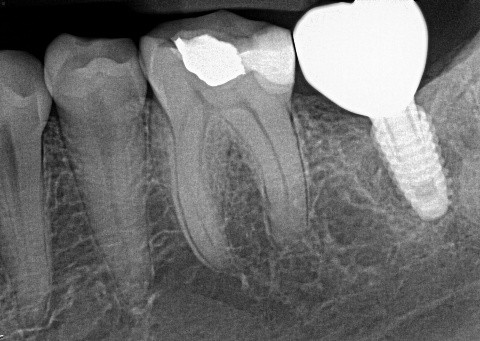

5 / 50

5. (Select ONE OR MORE correct answers)

The radiograph shows evidence of calculus on

6 / 50

6. (Select ONE OR MORE correct answers)